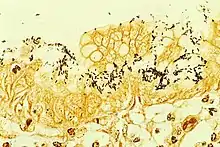

H. pylori can be demonstrated in tissue by Gram stain, Giemsa stain, H&E stain, Warthin-Starry silver stain, acridine orange stain, and phase-contrast microscopy. It is capable of forming biofilms.[26]